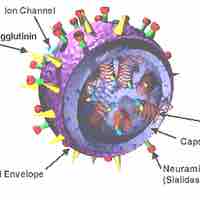

Different approches are used to target the initial and final steps of a virus life cycle.